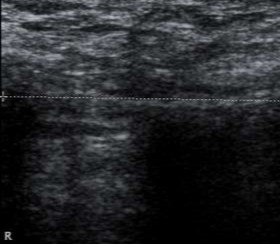

Hình 3.1. Hình ảnh siêu âm mô xơ ở vùng bẹn phải, xuất hiện đường tăng âm với bóng đen cản âm ở phía sau. Bệnh nhân: Ngô Tá Tr 69 tuổi, Nam.

Hình 3.2. Hình ảnh siêu âm mô xơ ở vùng bẹn trái, xuất hiện đường tăng âm với bóng đen cản âm ở phía sau. Bệnh nhân: Phan Văn S. 59 tuổi, Nam.

Hình 3.3. Hình ảnh siêu âm mô xơ ở vùng bẹn phải, xuất hiện đường tăng âm với bóng đen cản âm ở phía sau. Bệnh nhân: Lê Nh. 67 tuổi, Nam.

Mô xơ tạo thành quanh tấm lưới nằm ở vùng bẹn 100%, không có di chuyển và di lệch.